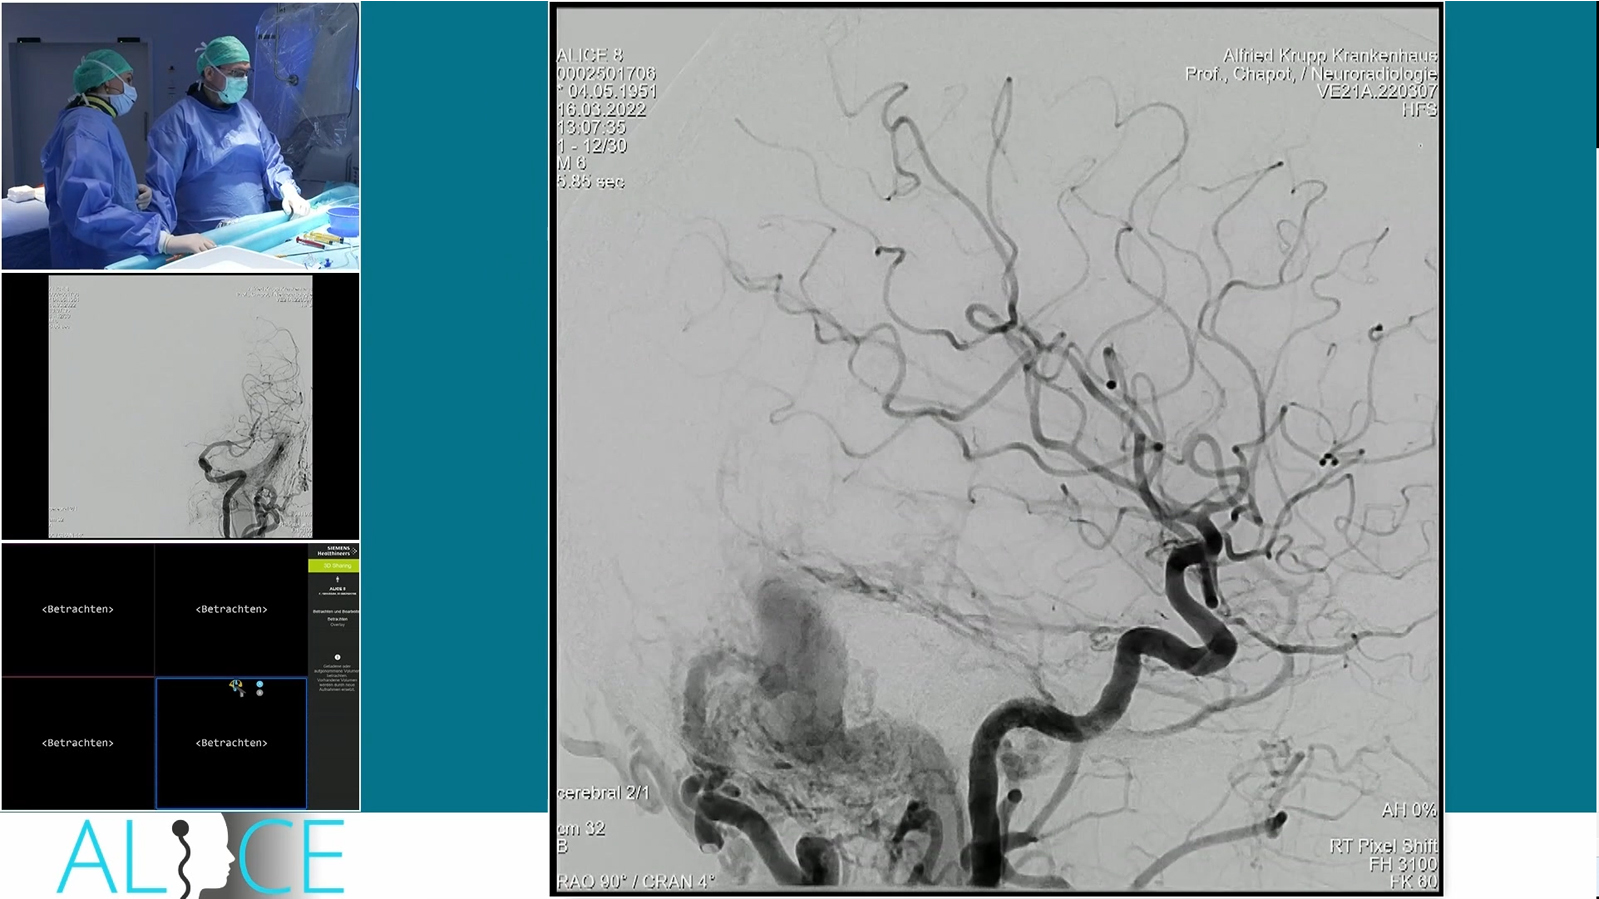

Essen: M1 stenosis with ICA tonsillar loop

Distal M2 occlusion thrombectomy with catch Mini